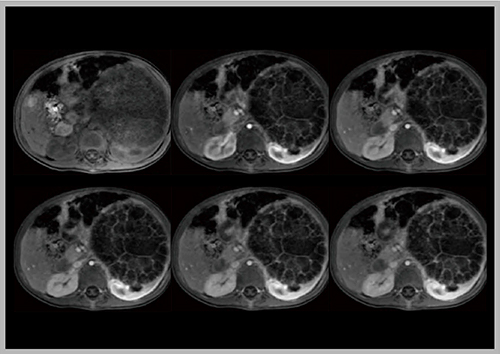

2)Stack-of-stars acquisition

stack-of-stars acquisitionはradial scanであり,動きに強いことが大きな特長であるが,さらに2つのアドバンテージがある。1つは,k-space中心のデータが均一にサンプリングされているため,どの部分を取っても再構成可能であり,例えば1つの画像を複数に分けて,後から時間分解能を変更できる。2つ目は,収集されたデータはボリューム全体の信号を有しており,それをプロットすると呼吸の動きが可視化できる。呼気のデータのみに重み付けして再構成すれば,呼吸性アーチファクトを低減するsoft gatingが可能である。この2つを組み合わせたsoft gated retrospective multiple phasesによって,navigator echo法を使用することなく,自由呼吸下でのダイナミックMR撮像が可能となる。

実際に動脈相の撮像を行うと,2分間で5相(1相あたり24秒)の画像が得られ(図6),必要であれば各画像を2つに分けて10相(1相あたり12.6秒)の画像にすることもできる。さらに,view sharingを併用すれば,1相あたり0.5秒で再構成した,明瞭かつ血管撮影に匹敵する高時間分解能な画像が得られ,非常に滑らかなTICも作成できる。

図6 Stack-of-stars acquisitionによる自由呼吸下での動脈相の画像(W.I.P.)